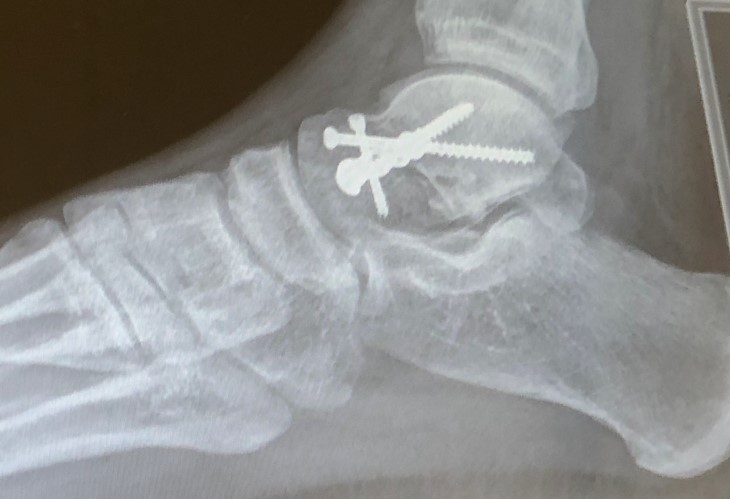

An x-ray of Liam Olson's right ankle after surgery showing metal screws.

Liam was rushed to hospital and soon had surgery to repair the damage. Five screws and plates were put into his ankle but it was clear there were going to be long-lasting effects.